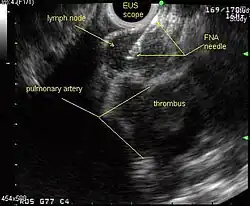

Endoscopic ultrasound (EUS) is an endoscopic technique where a miniaturized ultrasound probe is passed through the mouth into the upper gastrointestinal tract to investigate organs and structures close to the esophagus, stomach, or duodenum, such as the lung. In 1993, Wiersema published the first description of EUS to diagnose and stage lung cancer,[31] done by advancing a fine needle through the esophagus into adjacent lymph nodes. Numerous subsequent studies have shown this general methodology to be effective, very safe, minimally invasive, and very well tolerated. Given these advantages, many authorities think that EUS together with endobronchial ultrasound (EBUS) enhances lung cancer diagnosis and staging.[32]

Endobronchial ultrasound (EBUS)

As mentioned in the table, EUS cannot reliably access right sided paratracheal lymph node stations 2R and 4R and may not be optimal for the left sided paratracheal lymph node stations either. An adaptation of the endoscopic ultrasound scope originally designed for the gastrointestinal tract is known as endobronchial ultrasound (EBUS). The instrument is inserted into the trachea rather than the esophagus. There are two types of EBUS bronchoscopes available: radial catheter probe and convex probe EBUS (CP-EBUS),[37] but only the latter concerns us here. Early experience with mediastinal staging by CP-EBUS appears very promising with sensitivities ranging from 92 to 96 percent in 4 series comprising 70 to 502 patients.[38][39][40][41]

Combined ultrasound

EUS-FNA and EBUS-FNA are complementary techniques. EUS has the highest yield in the posterior inferior mediastinum, and EBUS is strongest for the superior anterior mediastinum. Some lymph node stations can only be accessed by one method and not the other (for example, station 2 and 4 L and 3 are hard or impossible to see by EUS, stations 5 and 8 cannot be biopsied by EBUS). Together, EBUS and EUS cover the entire mediastinum (except possibly station 6) and complete mediastinal staging should be possible with a combination of these two procedures. This combination could conceptually eliminate the need for most surgical mediastinoscopies and in fact be more comprehensive.

When combined, this approach has been termed "complete medical mediastinoscopy." EUS-FNA with EBUS may allow near-complete, minimally invasive mediastinal staging in patients with suspected lung cancer [42]